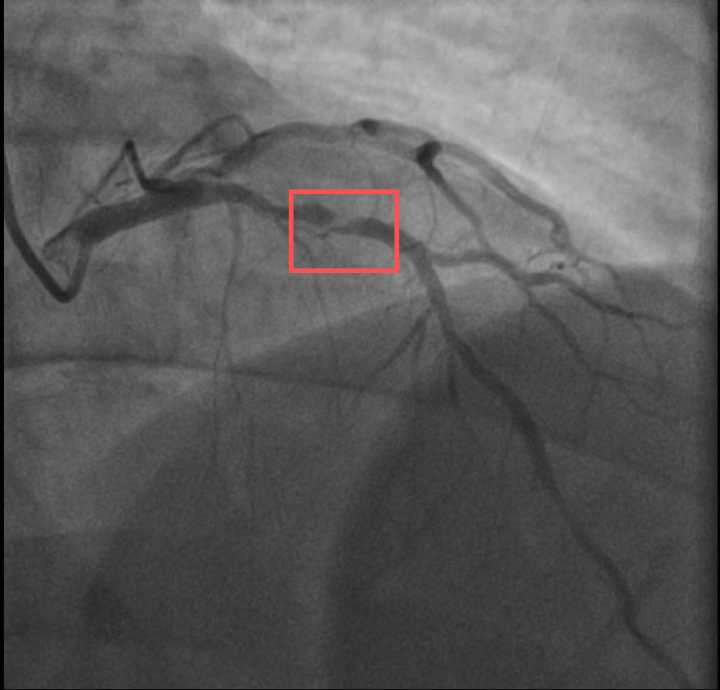

前不久,他带孩子到羽毛球场操练,手痒之下自己也上场,仅10分钟左右,就因心前区剧烈绞痛被送进了急诊。浙江医院心血管内科医师分析,剧烈运动导致这位患者心脏的不稳定斑块破裂,进而造成前降支近段次全闭塞。所幸送医及时,接受紧急介入治疗后,孙先生的身体险情被成功化解。

介入治疗前后影像图